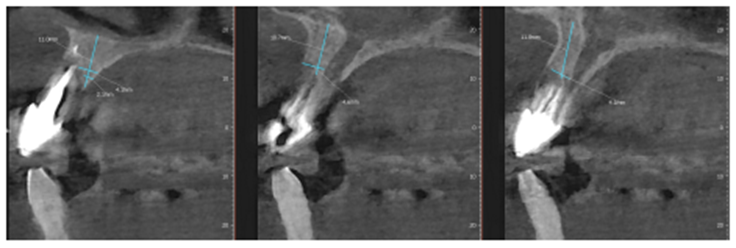

Paciente RV, do sexo masculino de 52 anos, compareceu a nossa clínica com queixa estética e funcional dos dentes incisivos centrais superiores. No exame clínico observou-se doença periodontal severa com presença de bolsa periodontal e perda óssea marginal maior do que 7 mm (Figura 1). Foi realizado em nossa escola (Beo – Ensino Odontológico Avançado) uma tomografia computadorizada para melhor planejamento cirúrgico do caso, onde confirmamos a necessidade de regeneração óssea guiada com membrana Cytoplast com reforço de titânio, devido à perda óssea vertical maior do que 7 mm (Figura 2). Após definição do planejamento cirúrgico, foi realizado a exodontia dos incisivos centrais superiores, limpeza cirúrgica da região e osteotomia periférica para melhor preparo do leito receptor do material de enxertia de lenta reabsorção Bio-Oss (Geistlich) e da membrana Cytoplast com reforço de titânio 30 mm X 40 mm (Figuras 3,4 e 5). Após estabilização da membrana, foi realizado a sutura com fio do tipo Cytoplast 3.0 mm devido a sua alta plasticidade, diminuindo o risco de deiscência de sutura (Figura 6).